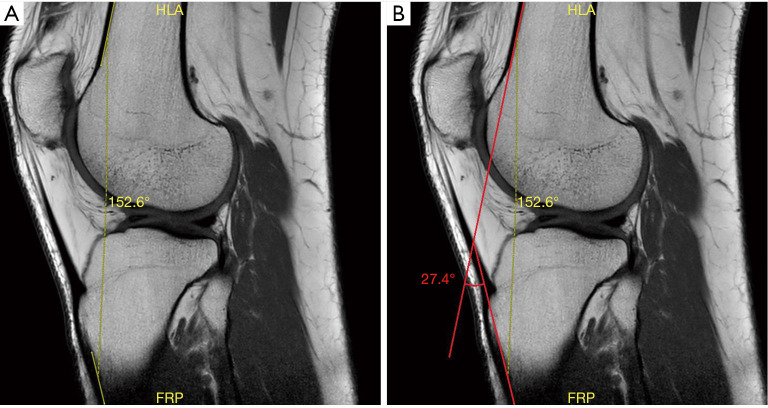

背景:活动范围(ROM)是骨科患者评估的一个重要方面。它可以通过确定患者在屈伸极限时所能达到的膝关节屈曲角(KFA)来测量膝关节的活动范围。与任何测量一样,所用方法的准确性和可靠性决定了其有效性。就 KFA 评估而言,磁共振成像(MRI)扫描与目前的黄金标准 X 光片相比,其一致性仍是未知数。本研究旨在评估和比较 X 光和核磁共振成像扫描测量 KFA 的可靠性:这项研究包括 80 名患者(94 个膝关节),他们因不同的膝关节病变前往膝关节专科门诊就诊,并接受了 X 光和核磁共振成像扫描。由两名训练有素的观察者分别在两个不同的时间点(相隔 8 周)测量侧位和 T1 加权矢状位成像视图(分别)的 KFA。然后对数据进行统计分析,并使用类内相关系数(ICC)计算观察者内部和观察者之间的可靠性:结果:X 射线的观察者内可靠性为 0.96(Pvs.16.8°),磁共振成像数据的观察者内可靠性为 0.96(P=0.022)。在这方面,X 光测量结果(46.4° 对 45.6°)无明显差异(P=0.182):结论:X 射线和磁共振成像都能以极高的可靠性测量 KFA。结论:X 射线和磁共振成像都能以极高的可靠性测量 KFA,但总体而言,X 射线测量优于磁共振成像测量,这主要是因为屏幕上可见图像的视野更大,更容易识别测量 KFA 所需的解剖标志。

Methods: This study included 80 patients (94 knees) who had attended a specialist knee clinic due to varying knee pathologies and undergone both X-ray and MRI scans. Lateral and T1-weighted sagittal imaging views (respectively) were used to measure KFA by two trained observers independently at two separate time points, 8 weeks apart. The data was then statistically analysed and intra- and inter-observer reliability calculated using the intraclass correlation coefficient (ICC).